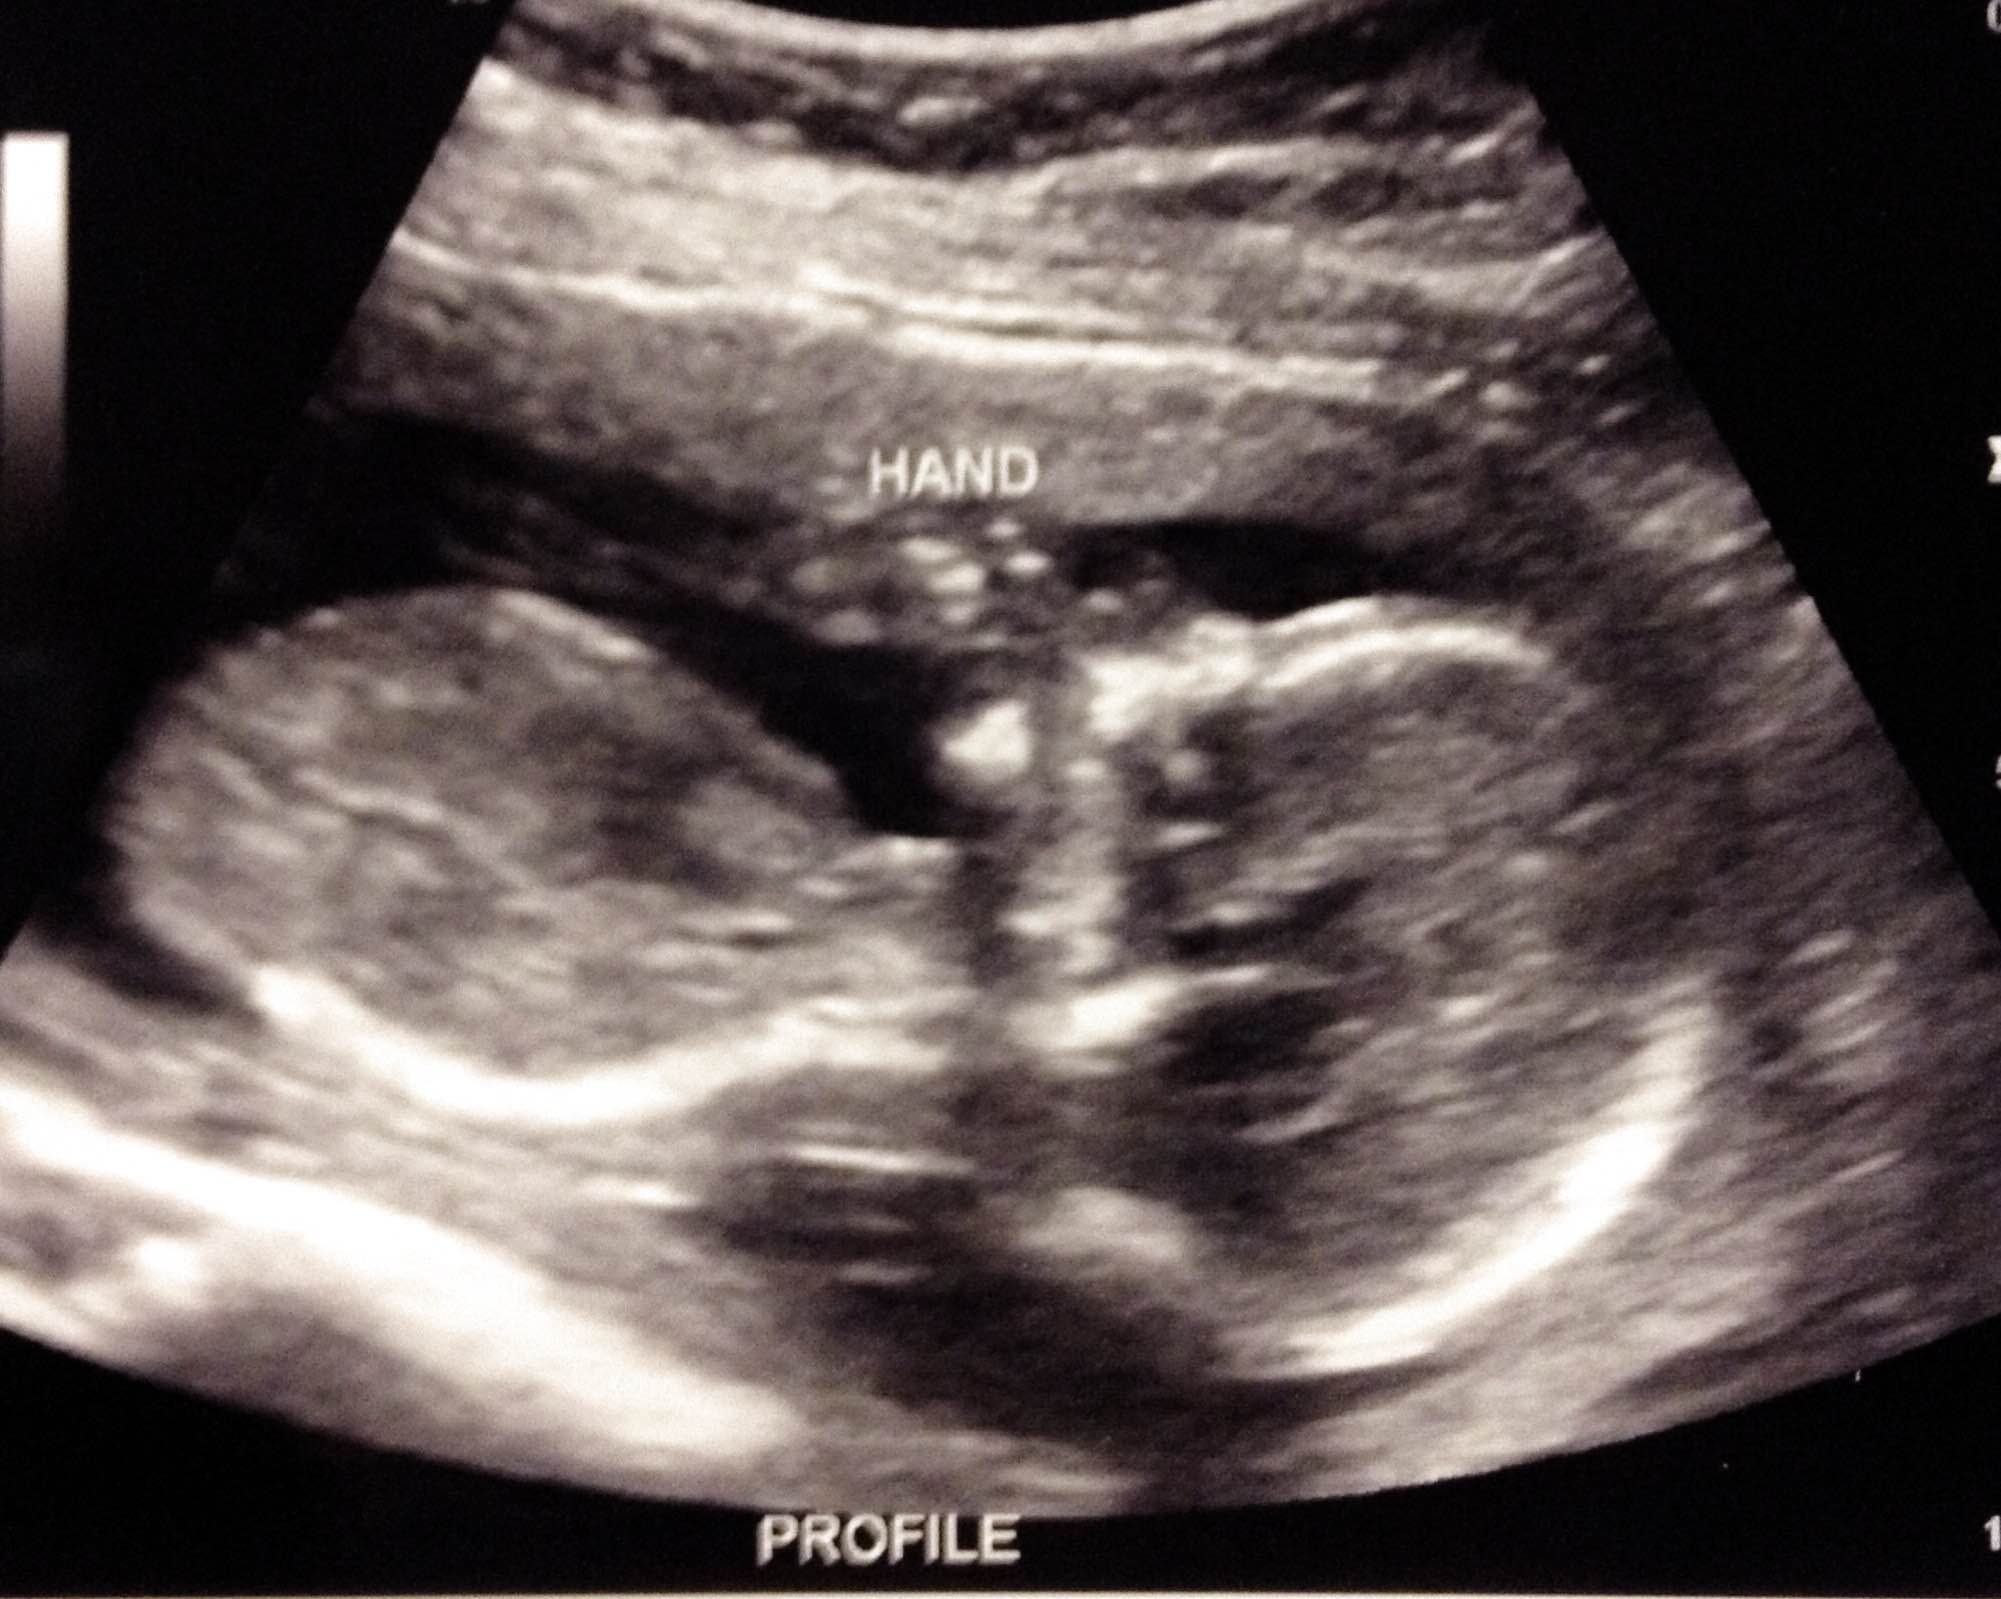

Yes! K is going to be a big sister at the end of March (or more likely, the beginning of April)! See?

Everything is going well so far. Even though I was sick for several months (still not sure I’m totally past it yet), it has definitely been my easiest pregnancy. Maybe being off gluten has been helpful or maybe the Unisom and B6 is working fantastically, but whatever it was it made for a much less miserable first trimester (and on into the second…). A little miserable at times, but much less so! We decided not to find out gender this time (a first for us) and man, does that make some people crazy! It is pretty entertaining how strongly people react to our decision. The baby’s nickname is Little Duck and that is good enough for us for now! We had our ultrasound a few weeks ago and everything looks perfect! I think the baby is probably a boy and have since the beginning, but the pregnancy itself has really been much more like N’s than K’s. K is fervently hoping for a girl. N wants a boy (he’s very outnumbered by girls in the family). And Josh doesn’t really have an opinion one way or the other. I think we’ll all be thrilled with whoever this little person turns out to be! One benefit to waiting to find out is that whoever is “wrong” won’t have months to be disappointed about it, because they’ll just be so excited that it is our BABY and it is HERE!

Little Duck is a busy little baby, always wiggly, and is growing right on schedule and has a strong, easy to find heartbeat. He/she is a pushy baby, too! I was feeling him/her push around in there long before the actual kicks started and even though there is plenty of kicking happening nowadays (strong enough for Josh and the kids to feel now and for us to see from time to time), there is still a lot of pushing around into weird positions. I suspect he/she will love swaddling, so there is still some resistance in the world to push against! Hopefully the second half of the pregnancy will be just as “easy”…no preterm labor scares like with K! We are so excited to meet him or her this Spring…19 weeks to go!